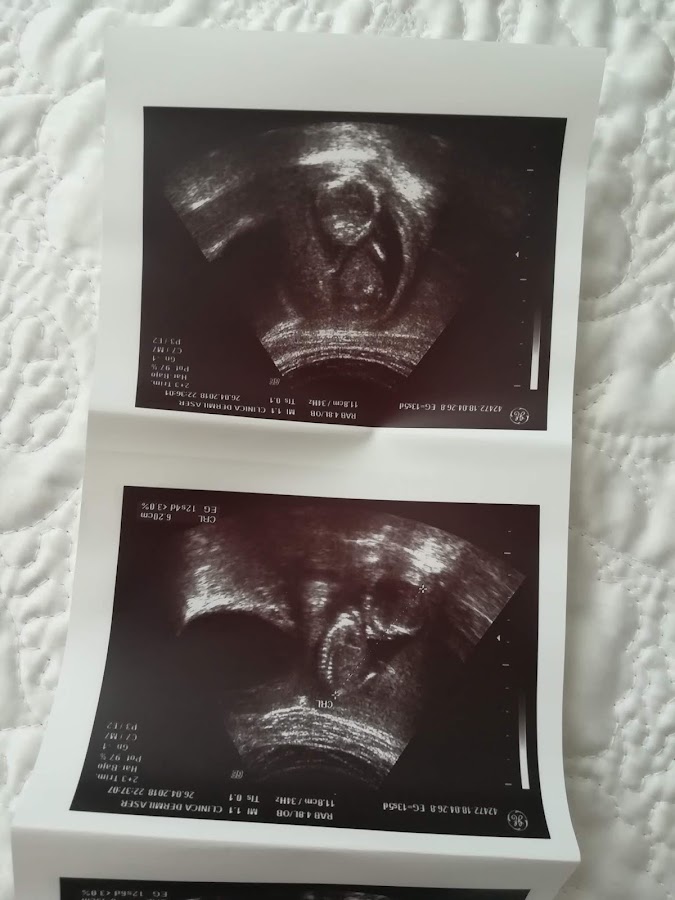

La eco de la semana 13 (13+5) me la hice el 26 de mayo , 2018. Al principio iba a ser una eco abdominal pero al final terminaron haciéndome otra vaginal porque con el quiste y tal no se veía bien. Vamos, lo de siempre.

Pude ver como movía las manitas y el latido de su corazón, que estaba perfecto, 150 pulsaciones. Lo que pasa que por el tamaño del feto me dijeron que estaba casi de 1 semana menos (12+6), cosa que yo se que no es...pero bueno, el gine se empeñó en eso y me cambió la fecha de parto a noviembre (en lugar del 27 de octubre). Yo no creo estar de 1 semana menos, sino de un par de días nada más , como se vió en la semana 10+6, que estaba de 10+4 según la eco. Lo que pasa que al ser otra máquina y tal, pues estas cosas pueden pasar. Yo he de reconocer que me cabreé un poco, pero no hay que darle mayor importancia. Si tu sabes cuándo te quedaste embarazada, esa es la fecha y ya está.

Le midió el pliegue nucal, o translucencia nucal -TN-, que estaba en 2.1. Y La longitud céfalo-caudal de 64.90 -CRL-.